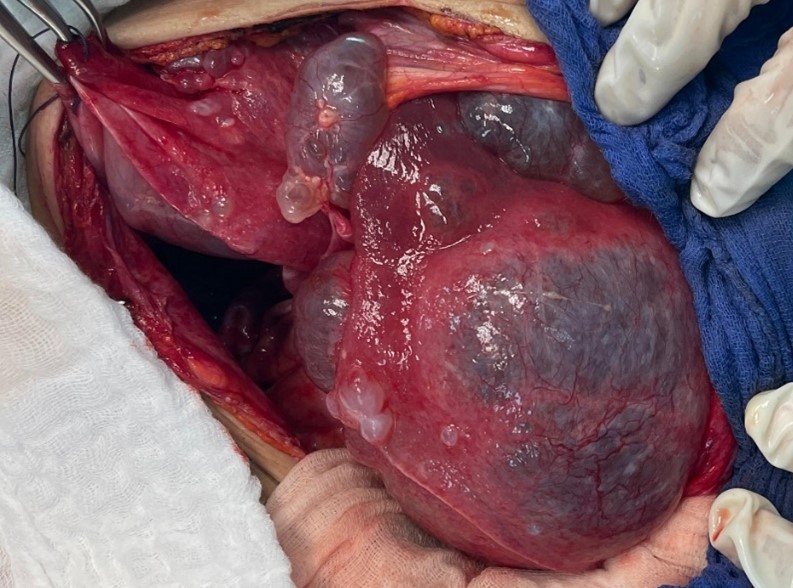

Figure 4: Per operative image after making the incision.

Intraoperative exploration revealed an enlarged liver extending to the left hypochondrium, containing multiple cysts, the largest of which occupied the entire right lobe of the liver, displacing the digestive structures (stomach, duodenopancreatic loop, transverse colon, and small intestine) towards the left side. The spleen appeared normal.

Figure 5: Per operative image showing a larger hepatic cyst located in the left liver.

The surgical procedure consisted of a fenestration of nearly all hepatic cysts, filled with transparent fluid, with wide drainage of both the peritoneal cavity and the residual cavity of the right hepatic cyst, using Salem tubes.